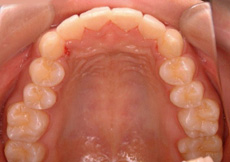

MTM(部分的な矯正)治療例4

矮小歯のあるケース

| 患者さまの年齢・性別 | 20代・男性 |

|---|---|

| 治療期間 | 5ヵ月 |

| 治療費(税込) | 242,000円 |

| 主訴 | 前歯の隙間が気になる。 |

| 診断名・主な症状 | 真ん中のスペースの閉鎖と右の矮小歯が裏側になってしまっている。 |

| 治療に用いた主な装置 | セルフライゲーションブラケット装置(デイモンシステム) |

| 治療内容 | 前歯の隙間を閉じ、右の裏側にある歯を前方に移動させています。上顎左右の前歯の隣の歯が矮小歯と言う本来より小さい歯のため、このままでは再度隙間があいてくる可能性があります。矯正治療後、この歯を少し大きくする治療が必要となります。 |

| 抜歯部位 | 非抜歯 |

| 通院回数・メンテナンス頻度 | 5回 |